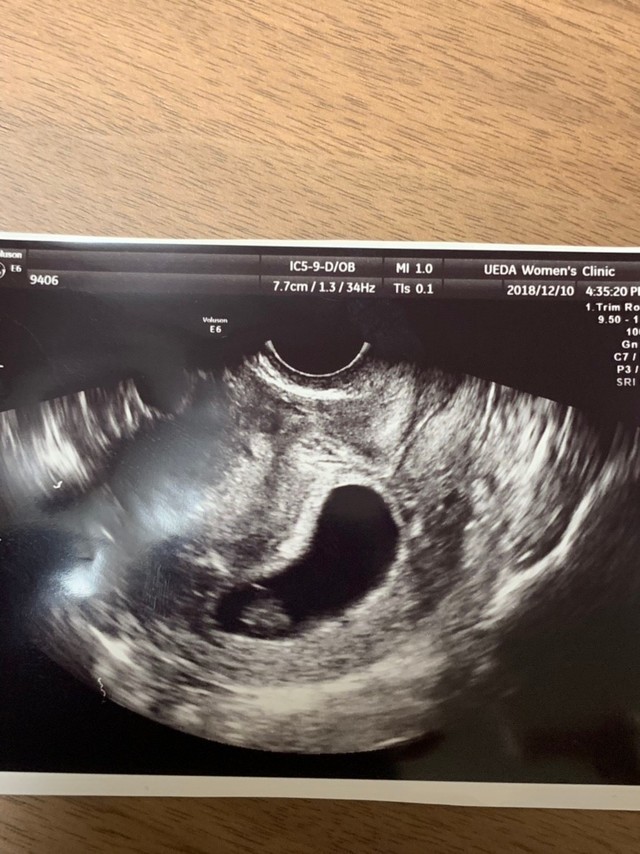

7週0日(7w0d・男の子)|わんちゃん さん(26歳)

エコー写真撮影時のエピソード:

妊娠が発覚した時、初めて撮ったエコー写真です。 当時ドキドキしながら行った婦人科で、ドラマで見たことしかなかったエコー写真を手にした時、とてもうれしい気持ちと、私が母になれるのかという不安と、こんなに小さい赤ちゃんがお腹に居るという感動は忘れられません。

当時つわりもありましたが、赤ちゃんの大きさは7ミリです、と先生からお話されてたった1センチも無い赤ちゃんが生きてる証拠なんだと、それ以降のつわりも愛おしく感じました。